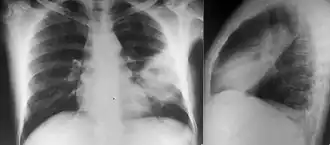

Various imaging modalities can also help with the diagnosis of melioidosis. In acute melioidosis with the spreading of the bacteria through the bloodstream, the chest X-ray shows multifocal nodular lesions. It may also show merging nodules or cavitations. For those with acute melioidosis without the spread to the bloodstream, chest x-ray most commonly shows upper lobe consolidation or cavitations.[9] In chronic melioidosis, the slowly progressing of upper lobe consolidation of the lungs resembles tuberculosis.[9] For abscesses located in other parts of the body apart from the lungs, especially in the liver and spleen, CT scan has higher sensitivity when compared with an ultrasound scan. In liver and splenic abscesses, an ultrasound scan shows "target-like" lesions while CT scan shows "honeycomb sign" (abscess with loculations separated by thin septa) in liver abscesses.[9] For melioidosis involving the brain, MRI have higher sensitivity than a CT scan in diagnosing the lesion. MRI shows ring-enhancing lesions for brain melioidosis.[9]